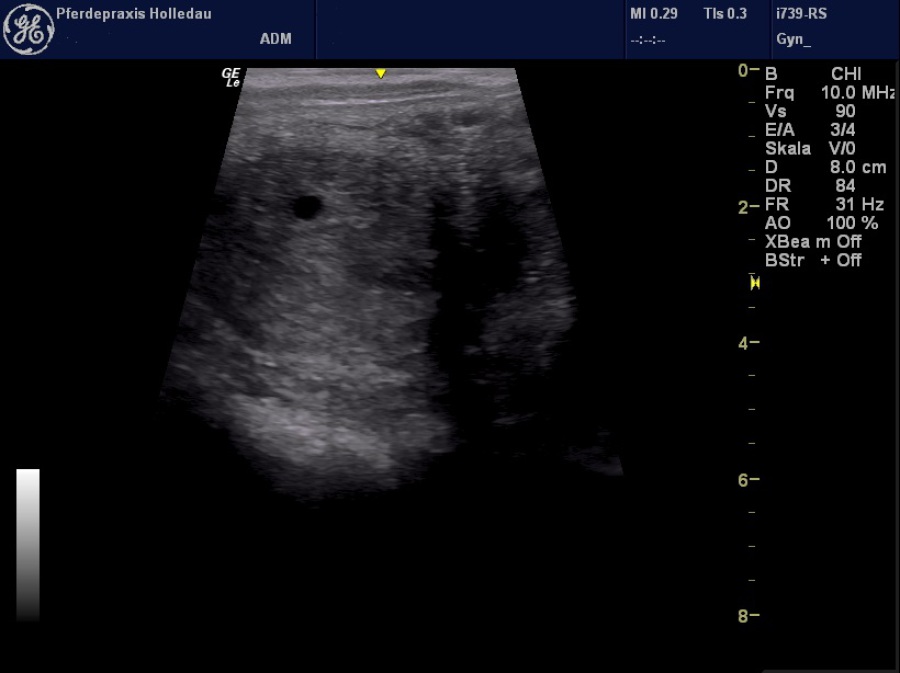

Ultraschallbild: Uterus mit Rosseanzeichen (Radspeichen)

Ultraschallbild: Endometriumszyste (Gebärmutterzyste)